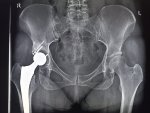

Здравствуй двачик, пишет вам простой рентгенолог из мухосранской поликлиники, сегодня я буду флексить зарплатой за ноябрь! Аж ПЯТЬДЕСЯТ ТРИ ТЫЩИ ПЕРЕВЕДУТ! С пруфом! А чего достигли вы? Ну и в доктора тож поиграем! Я буду вам картинки показывать, а вы пиздецомы находить! Найдите пиздецому на фтчк! Отчет еще по фог считать квартальный и годовой сегодня :-(